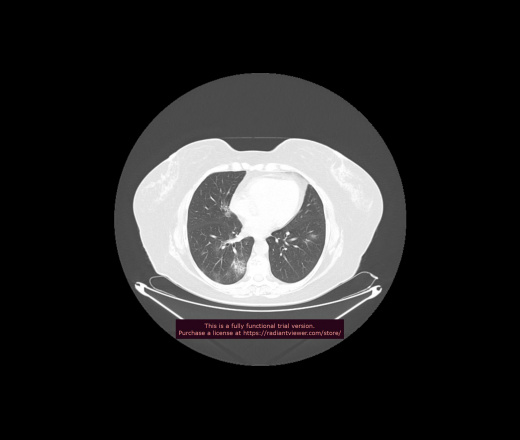

Уважаемые коллеги, если имеется интерес, сможете ли Вы спрогнозировать дальнейшее +-одинаковое течение процесса у 4 данных разных пациентов? Зацепиться где-то можно очень просто, где-то нельзя.